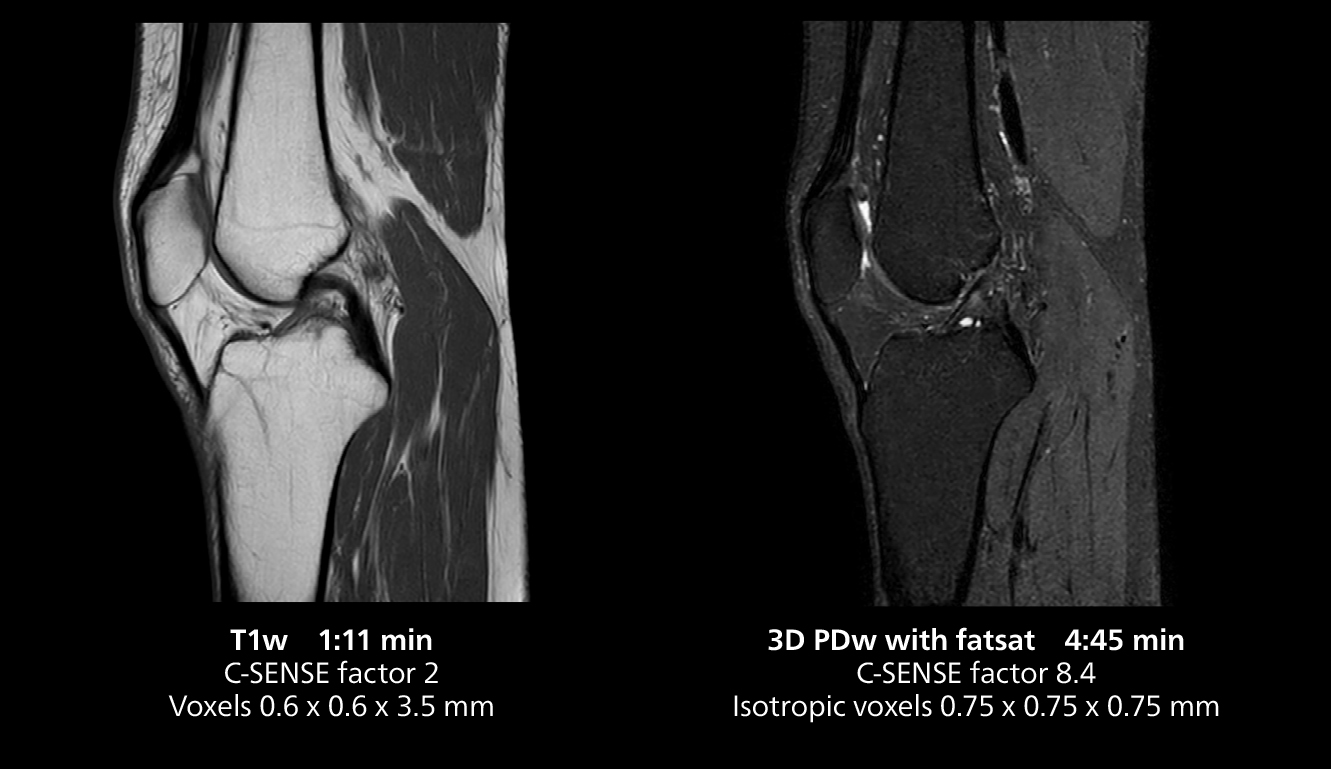

3D knee imaging

The isotropic high resolution 3D sequence in this MRI case allows for reformatting to obtain other orientations with high quality. Acquired on the MR 5300 system.

3D knee imaging

The isotropic high resolution 3D sequence in this MRI case allows for reformatting to obtain other orientations with high quality. Acquired on the MR 5300 system.

The MR 5300 with Compressed SENSE is up to 50%** faster for many exams. It can provide routine exams in less than 5 minutes and whole-body exams in less than 20 minutes. Saint-Augustin has taken advantage of that speed to create highly efficient protocols. The hospital’s standard stroke protocol is just about 8 minutes, and standard ENT, prostate PIRADS staging, and endometriosis studies all clock in at just about 10 minutes.***

“We have more speed in 3D sequences,” Dr. Gellée states. “With Compressed SENSE, we can replace two or three 2D scans withone high-quality 3D scan. High quality additional orientations are then obtained by post-processing of the 3D data set, thus saving scanning time.”